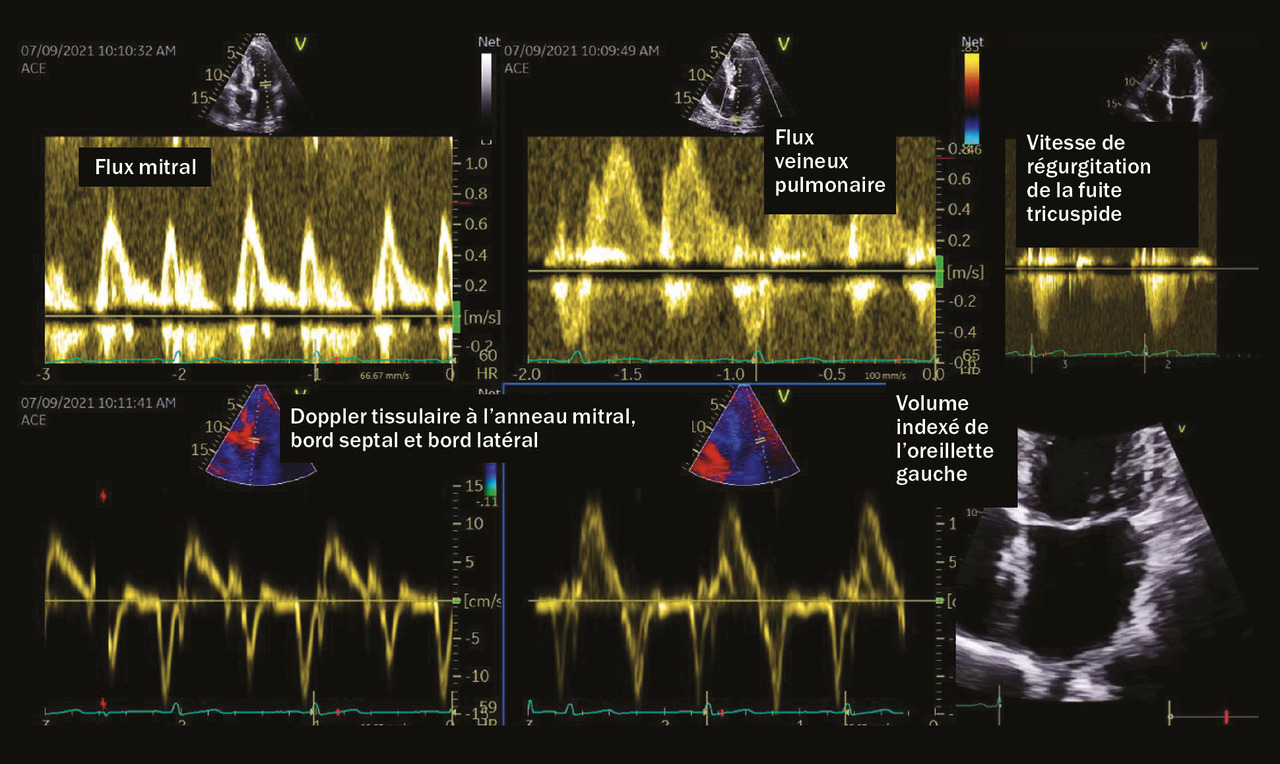

Lors de l’échocardiographie transthoracique, l’évaluation du strain (capacité de déformation myocardique) atrial s’avère désormais encouragée par les dernières recommandations ; elle permet d’améliorer la performance de l’échocardiographie, examen fondamental pour le diagnostic positif et phénotypique de l’insuffisance cardiaque à fraction d’éjection préservée. (fig. 3).26

La réalisation d’un test dynamique semble très prometteuse. En effet, les ventricules gauche et droit font face à une postcharge élevée au repos mais c’est bien dans les conditions de stress que l’équilibre est rompu et que le patient manifeste des signes d’insuffisance cardiaque droite, gauche ou mixte selon les phénotypes.27, 28 Effectuer un test d’effort sous-maximal permettrait donc de mettre en évidence une absence d’adaptation au stress : absence de réserve contractile mais aussi sans doute de capacité de relaxation (e’ en Doppler tissulaire). Cette trop grande rigidité et cette absence d’adaptation aux changements de conditions de charge expliqueraient certainement les symptômes et permettraient de distinguer l’insuffisant cardiaque à fraction d’éjection préservée du patient âgé hypertendu avec remodelage ventriculaire gauche concen­trique.

Plusieurs travaux ont été menés dans ce sens. Récemment, il a même été proposé une méthode standardisée pour effectuer cette échocardiographie d’effort sous-maximale afin de tester le patient ICFEP.29

Dans la pratique clinique, on observe que les ventricules, rigides, ne s’adaptent pas à l’augmentation de la postcharge liée à l’effort et que plusieurs signes apparaissent, dès les premiers coups de pédale :

– une fuite tricuspide avec une augmentation des pressions pulmonaires estimées (au-delà de 60 mmHg en moins de 4 à 5 minutes) ;

– une absence d’augmentation de S’ et e’ tel qu’enregistré à l’anneau mitral (en Doppler tissulaire pulsé) avec, de fait, une augmentation rapide du rapport E/e’ ; une fuite mitrale est aussi possible (tableau 2) ;

– une absence d’augmentation du débit cardiaque, du volume d’éjection systolique comme du strain global longitudinal.30, 31

Il semble donc très pertinent d’utiliser l’échocardiographie d’effort en cas de doute diagnostique.